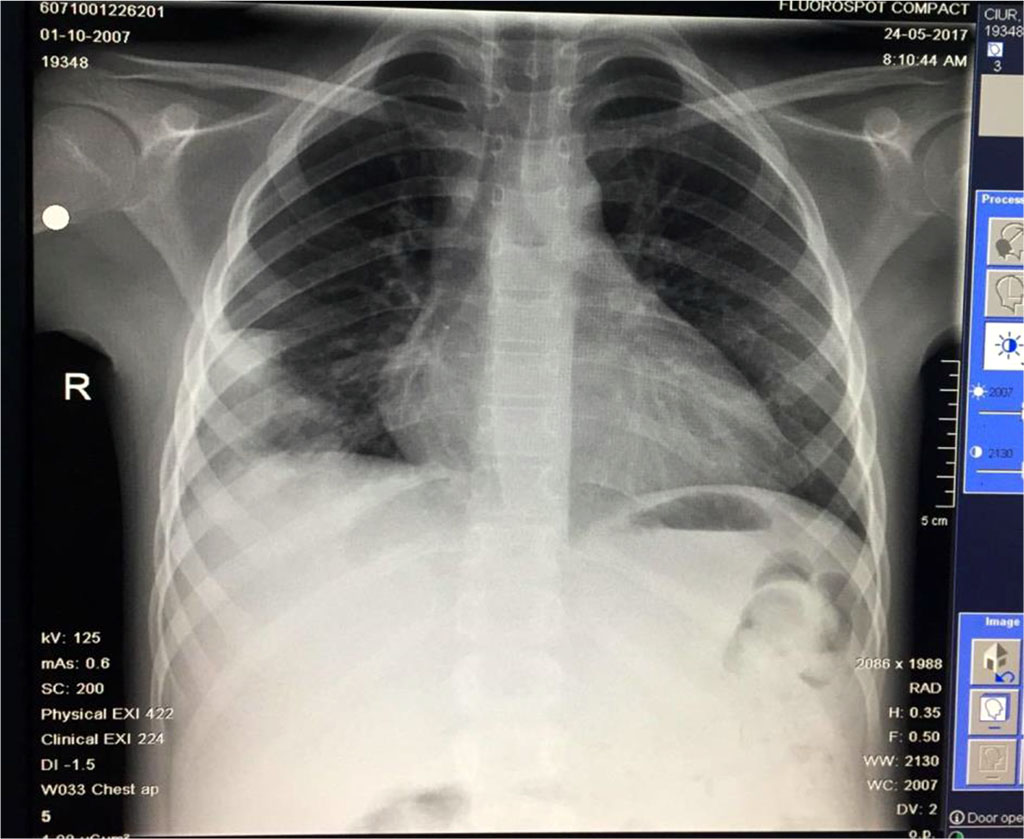

Seven days after the pleural drainage, another chest x-ray was performed. It revealed the maintaining of a non-homogeneous opacity in medium 2/3 of the right hemithorax (Fig. 8). Thus, a video-assisted thoracoscopy (VAT) pleuropulmonary decortication was done (Fig. 9). A subsequent chest x-ray revealed an ameliorated image (Fig. 10). Post-operatory evolution was slowly favorable despite the association between large spectrum antibiotic therapy and systemic antifungal therapy. The patient also needed supportive with rehydration perfusion, immunotherapy and blood transfusion for about one month.

Fig. 8. Non-homogeneous opacity in medium 2/3 of the right hemithorax